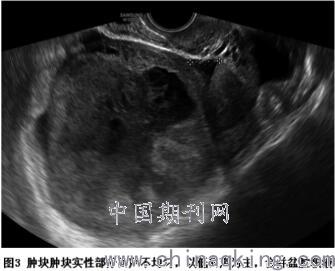

(1)病灶位置:均为单发,左右卵巢各9例(50%)。(2)病灶大小:最大径线8~27cm,平均15.29cm。(3)病灶回声:肿块均呈囊实性混合回声,以囊性为主(囊性成分≥50%)10例,以实性为主(囊性成分<50%)8例。囊性部分呈蜂窝状或不规则网格状改变,内透声程度不一(图1);实性部分回声不均匀,以低回声及中等回声为主(图2、3)。(4)彩色多普勒:15例(83%)中等及以上血流信号(图4),3例(17%)少量或无明显血流信号。(5)频谱多普勒:5例未检测阻力指数(RI),13例RI0.25~0.61,平均RI0.45。(6)其中12例(66.7%)合并盆腹腔积液。(7)盆腹腔脏器均受不同程度推挤。